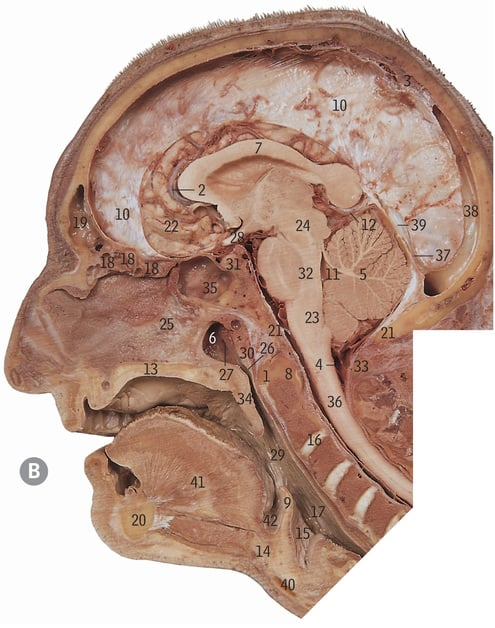

24

Midbrain

32

Pons

23

Medulla oblongata

4

Clivus

5

Cerebellum

17

Inferior colliculus

41

Superior colliculus

Cerebral aqueduct

2

Cisterna magna